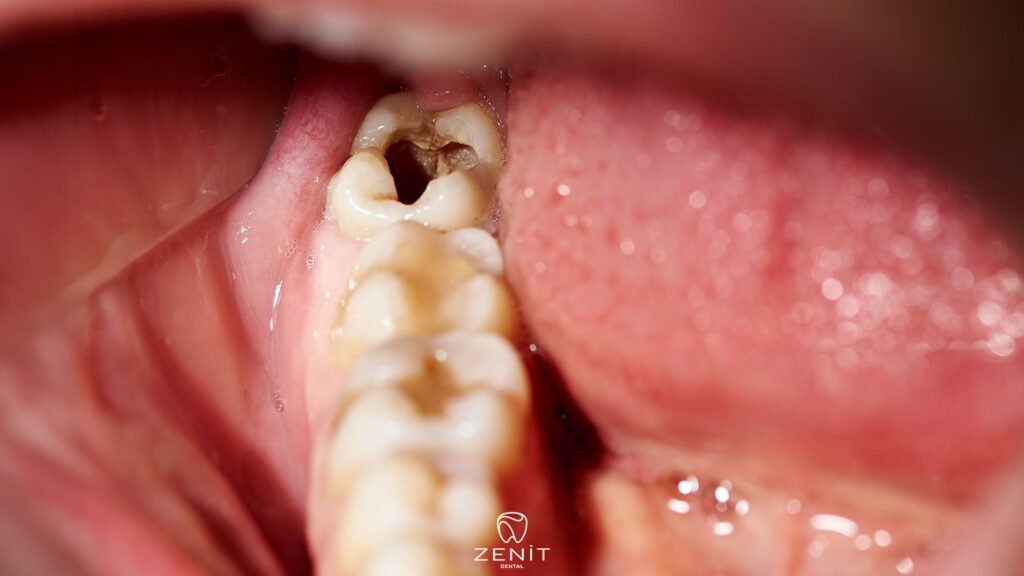

Another important reason is the tiny gaps that can form between the filling and the tooth over time. These gaps may be too small to see, but they create a perfect space for bacteria. When food particles and microorganisms settle in these areas, decay usually begins under or around the filling. This is why people sometimes hear that “there is decay under the filling,” which is exactly how it happens.

Decay in a filled tooth often progresses silently. In the beginning, you may not feel anything at all, and it might even seem fine for years. That’s why many people only realize the problem once it has progressed. But as the decay deepens, the body starts to give small warning signs.